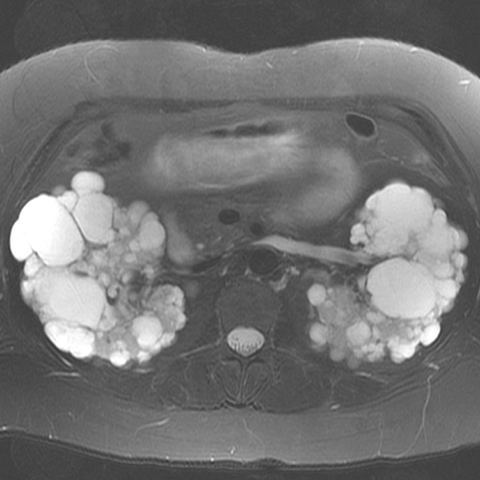

40-year-old woman with progressive renal failure and palpable abdominal masses [1 of 2]